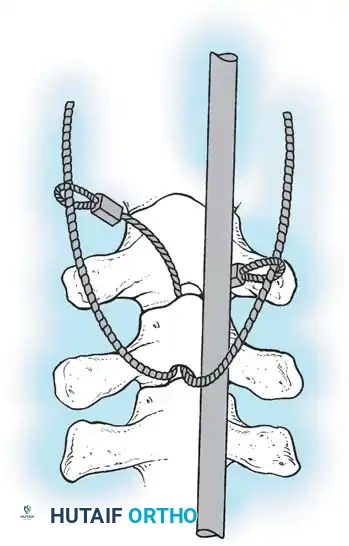

The Moe Technique (Lumbar Spine)

In the lumbar spine, the facet joints are oriented in a more sagittal plane, necessitating a modified approach.

Fig. 38-27: The Moe technique adapted for lumbar facet fusion, addressing the sagittal orientation of the joints.

- Utilize a small osteotome or a needle-nose rongeur to resect the adjoining joint surfaces.

- This creates a distinct rectangular defect within the sagittally oriented joint space.

- Pack this defect forcefully with cancellous bone graft.

- Proceed to decorticate the entire exposed posterior elements (laminae and transverse processes) using Cobb gouges, always directing force away from the spinal canal.